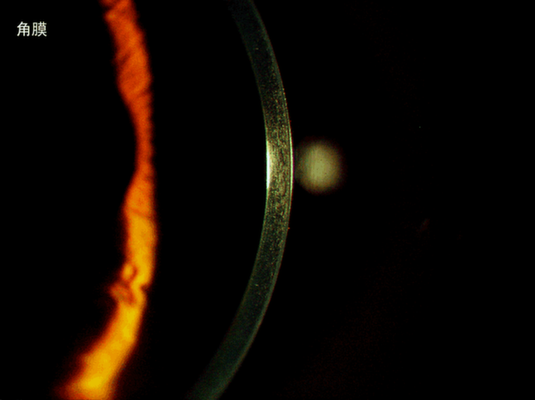

角膜 语文 四年级.gif